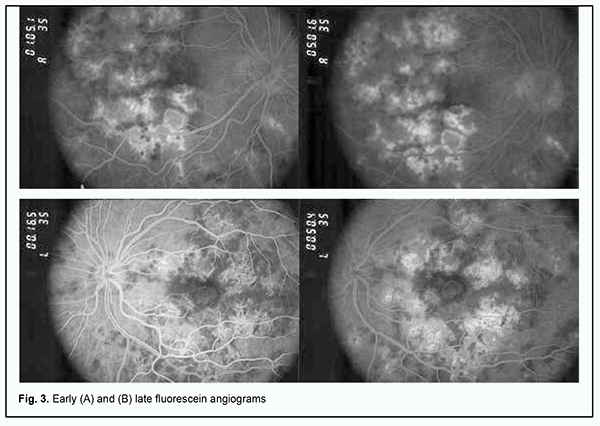

Lesions in both eyes showed hypofluorescence in the early phases of FA. The degree of hypofluorescence gradually increased with time, with the formation of areas of RPE atrophy with mildly redistributed pigment, and lesions of various severities observed in the fundus (Fig. 3A).

In the late phase of FA, hyperfluorescent regions could be seen throughout the fundus, and hyperfluorescent pinpoint changes could be observed in areas of serous retinal detachment. Hyperfluorescent optic disk was noted in the late phase of FA (Fig. 3B). In both eyes, OCT showed hyperreflective lesions at the level of photoreceptors, destruction of the outer photoreceptor and RPE layers, foci of proliferation and RPE detachment (Fig. 4).